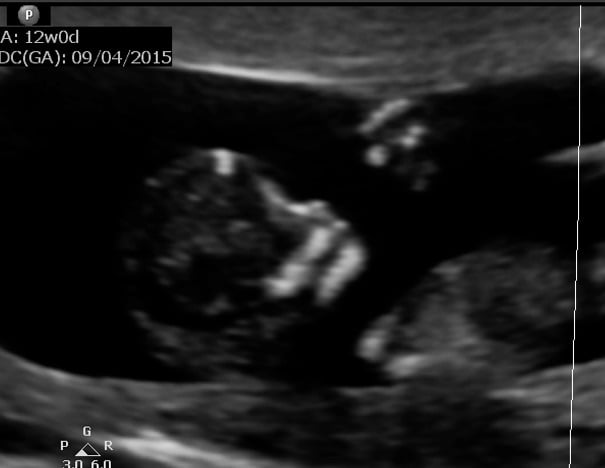

I got one at 7w and then today at 12w.(surprise extra u/s since the doppler couldn't pick up the heartrate!) Our little baby has grown a lot in 5 weeks!